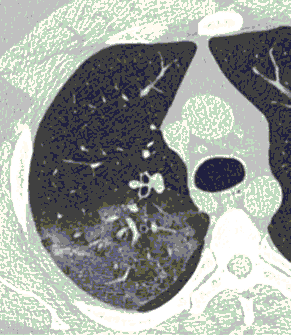

4.3. ЛУЧЕВАЯ ДИАГНОСТИКА COVID-19

Методы лучевой диагностики применяют для выявления COVID-19 пневмоний, их осложнений, дифференциальной диагностики с другими заболеваниями легких, а также для определения степени выраженности и динамики изменений, оценки эффективности проводимой терапии.

КТ имеет высокую чувствительность в выявлении изменений в легких, характерных для COVID-19. Применение КТ целесообразно для первичной оценки состояния ОГК у пациентов с тяжелыми прогрессирующими формами заболевания, а также для дифференциальной диагностики выявленных изменений и оценки динамики процесса. КТ позволяет выявить характерные изменения в легких у пациентов с COVID-19 еще до появления положительных лабораторных тестов на инфекцию с помощью МАНК. В то же время, КТ выявляет изменения легких у значительного числа пациентов с бессимптомной и легкой формами заболевания, которым не требуется госпитализация. Результаты КТ в этих случаях не влияют на тактику лечения и прогноз заболевания при наличии лабораторного подтверждения COVID-19. Поэтому массовое применение КТ для скрининга асимптомных и легких форм болезни не рекомендуется. При первичном обращении пациента с подозрением на COVID-19 рекомендуется назначать КТ только при наличии клинических и инструментальных признаков дыхательной недостаточности (SpO2 < 95%, ЧДД > 22).